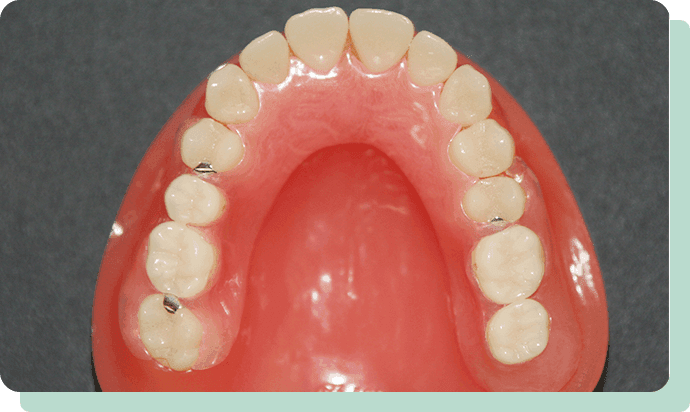

歯が少なくなり、どうしても入れ歯が安定しない場合は、インプラントを最小限適用して、安定させることも可能です。

写真の方の場合は、ホックのような材料を採用。

パチッと差し込む方法で装着するので、維持力が大きく増しました。

入れ歯を安定化させることで、しっかり噛めるというメリットもあります。

インプラント義歯